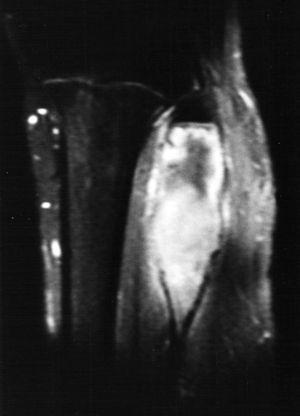

Fig. 5.--Secuencia coronal T1-ES. La lesión aparece homogéneamente hipointensa, de comportamiento expansivo, limitada superiormente por la phisis.

Fig. 6.--Secuencia STIR coronal. Se diferencian los dos componentes. El superior hipointenso con una halo de hiperseñal y el inferior hiperintenso sin asociarse a masa de partes blandas.

La RM permite una clara delimitación entre el hueso normal y el tumoral. Generalmente aparece hipointenso tanto en las secuencias T1 como T2, como los linfomas o los tumores fibrosos, debido a la densa matriz conectiva, y para algunos autores debido a la relativa hipocelularidad, lo que significa una disminución de los protones móviles6. Otros autores recogen otros hallazgos, como la presencia de una pseudocápsula, focos de necrosis, niveles líquido-líquido dentro del tumor8 y, en ocasiones, un comportamiento hiperintenso en las secuencias T22,4. En nuestro caso se identificaban dos componentes diferentes dentro de la misma lesión de diferente señal en las secuencias T2. El componente superior es hipointenso y el inferior de intensidad intermedia. En las secuencias dinámicas postgadolinio intravenoso, el componente superior mostraba un leve realce periférico en fase tardía con prácticamente nulo realce en fase precoz y el componente inferior presentaba intenso realce en fase precoz, que persistía en fases tardías.